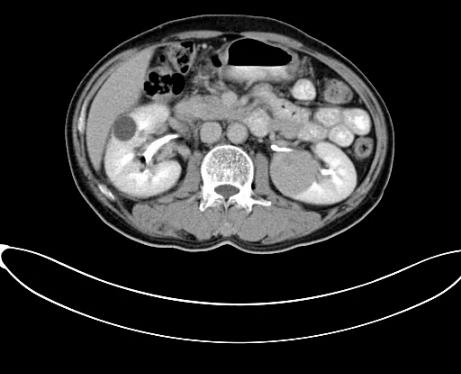

2017年9月29日,从CT影像看到右肾情况更为严重。为减缓肿瘤增长的速度,专家进行商议后,最终决定由牛立志教授主刀为安图叔叔进行了右肾肿瘤冷冻消融术。手术开始后,牛立志教授在CT和超声引导下,同时使用两根冷冻针固定病灶,精准灭活肿瘤;术后很成功无不良反应。术后一周进行第二次双肾肿瘤冷冻消融术。安图叔叔儿子笑道:“当时真的很紧张,医生劝慰我无须担心,都交给他们,我们都很清楚知道父亲的病情,真的很感谢也很庆幸我父亲遇到复大的医护人员,免受开刀之痛。住院期间医护人员很尽心尽力的照顾父亲,手术的成功离不开他们的辛劳付出。”